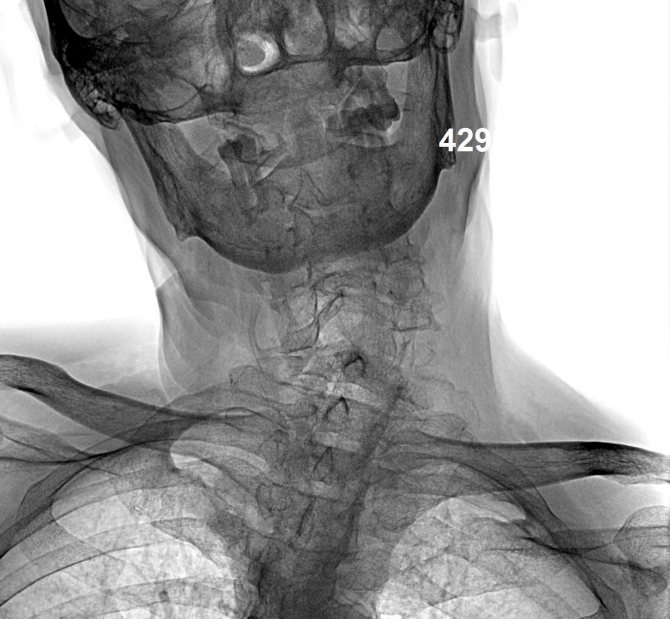

Для спондилёза шейного отдела характерно следующее.

- Боль в окципитальной области, которая носит пульсирующий характер, иррадиируется в верхние конечности, в челюсть. Является результатом корешкового синдрома.

- Ограничение подвижности шеи и рефлекторный спазм мышц. Эти симптомы связаны с наличием скобок, которые образовались в результате полного сращения остеофитов.

- Интенсивные головные боли. Причиной головной боли и мигрени является сдавливание. Если оно сильное, это может привести к обмороку.

В случае симптомов, которые вызывают подозрение на спондилёз и спондилоартроз, необходимо обратиться к невропатологу, травматологу, хирургу, либо ортопеду. Для дифференциальной диагностики специалист в первую очередь должен собрать анамнез. Больной в точности описывает, что его беспокоит, есть ли в семье человек, который жалуется на такие же симптомы, связана ли профессия пациента и его жизнедеятельность с повышенным риском травматизма и с ношением тяжести, есть ли в его анамнезе перенесенные травмы и операции на позвоночник.

Пальпацией и неврологическим исследованием специалист устанавливает болезненность в той или иной области. Врач обращает внимание на характер дыхания пациента и на позу, в которой он сидит. Наличие вынужденной позы эмбриона и поверхностное дыхание позволяет подозревать болевой синдром при спондилёзе и спондилоартрозе. После субъективного и объективного исследования без использования диагностической техники, пациента обследуют инструментальными методами, которые являются более информативными. Самым доступным методом является рентгенография. Проводят ее как в прямой, так и в боковой проекциях. Для диагностики также применяется компьютерная томография. Этот метод дороже, но эффективней. Признаками спондилёза и спондилоартроза при проведении КТ будут: